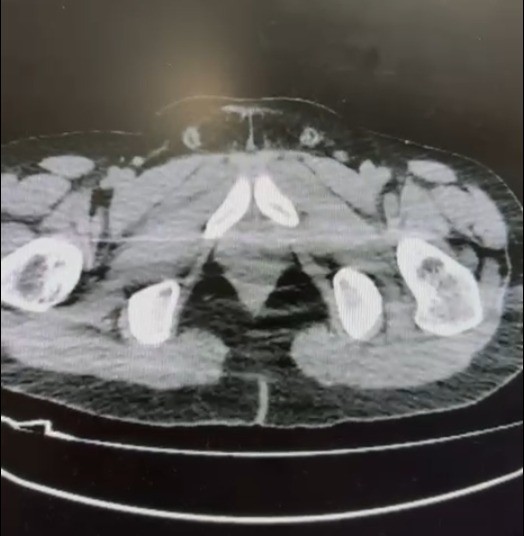

Sözkonusu torbacıların uyuşturucu maddeyi yutma yönteminde çeşitli materyaller kullanarak uyuşturucu maddeyi yuttukları, Nevşehir Devlet Hastanesinde yapılan kontrollerdeki röntgen çekiminde de net bir şekilde görüldü.

Yapılan aramalarda da 101 kapsül halinde 722 Gr. Metamfetamin Maddesi, 1 adet Hassas Terazi, Uyuşturucu Madde sevkiyatında yutma yönteminde kullanılan muhtelif materyaller ile Uyuşturucu Madde Ticaretinden Elde Edilen 20.210 TL, 1.320 Euro ve 10 ABD Doları paraya el konuldu. Torbacılar S. B. ve O. R. isimli şahıslar TCK 188-Uyuşturucu Madde Ticareti Yapmak suçundan Nevşehir Cumhuriyet Başsavcılığına sevk edilmek üzere gözaltına alındılar.